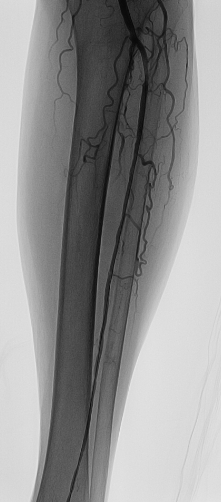

术中李龙虎主任结合造影结果,实施了手术:开通左股浅动脉改善大腿血流,开通左胫前动脉改善小腿及足部血流。送入JR4.0 导引导管,泥鳅导丝多次尝试下可通过股浅动脉远段闭塞病变并送至胫前动脉闭塞病变前,交换V18导丝,先以5.0*150mm外周PTA Catheter扩张股浅动脉中远段病变(图3),复查造影见股浅动脉中远段病变残余狭窄明显改善,再多次尝试下V18导丝可通过胫前动脉闭塞病变至其远段,再送入3.0*150mm外周PTA Catheter由远及近预扩张胫前动脉(图4),复查造影示胫前动脉残余狭窄改善,再送2.530mm药物洗脱外周球囊至胫前动脉扩张释放药物(6atm180s), 复查造影示胫前动脉无明显残余狭窄(图5),血管无穿孔、夹层,远段血运良好。再送5.0*150mm外周PTA Catheter充分扩张股浅动脉中远段病变,再于股浅动脉中远段病变由远及近串联植入支架,复查造影示支架贴壁良好(图6),血管无穿孔、夹层,远段血运良好。术毕,退出鞘管,以血管缝合器缝合穿刺口,无菌方纱包扎,安返病房,术程顺利,病人无不适。术后左下肢足背动脉搏动良好,左下肢疼痛消失,无间歇性跛行。

图3 股浅动脉球囊扩张